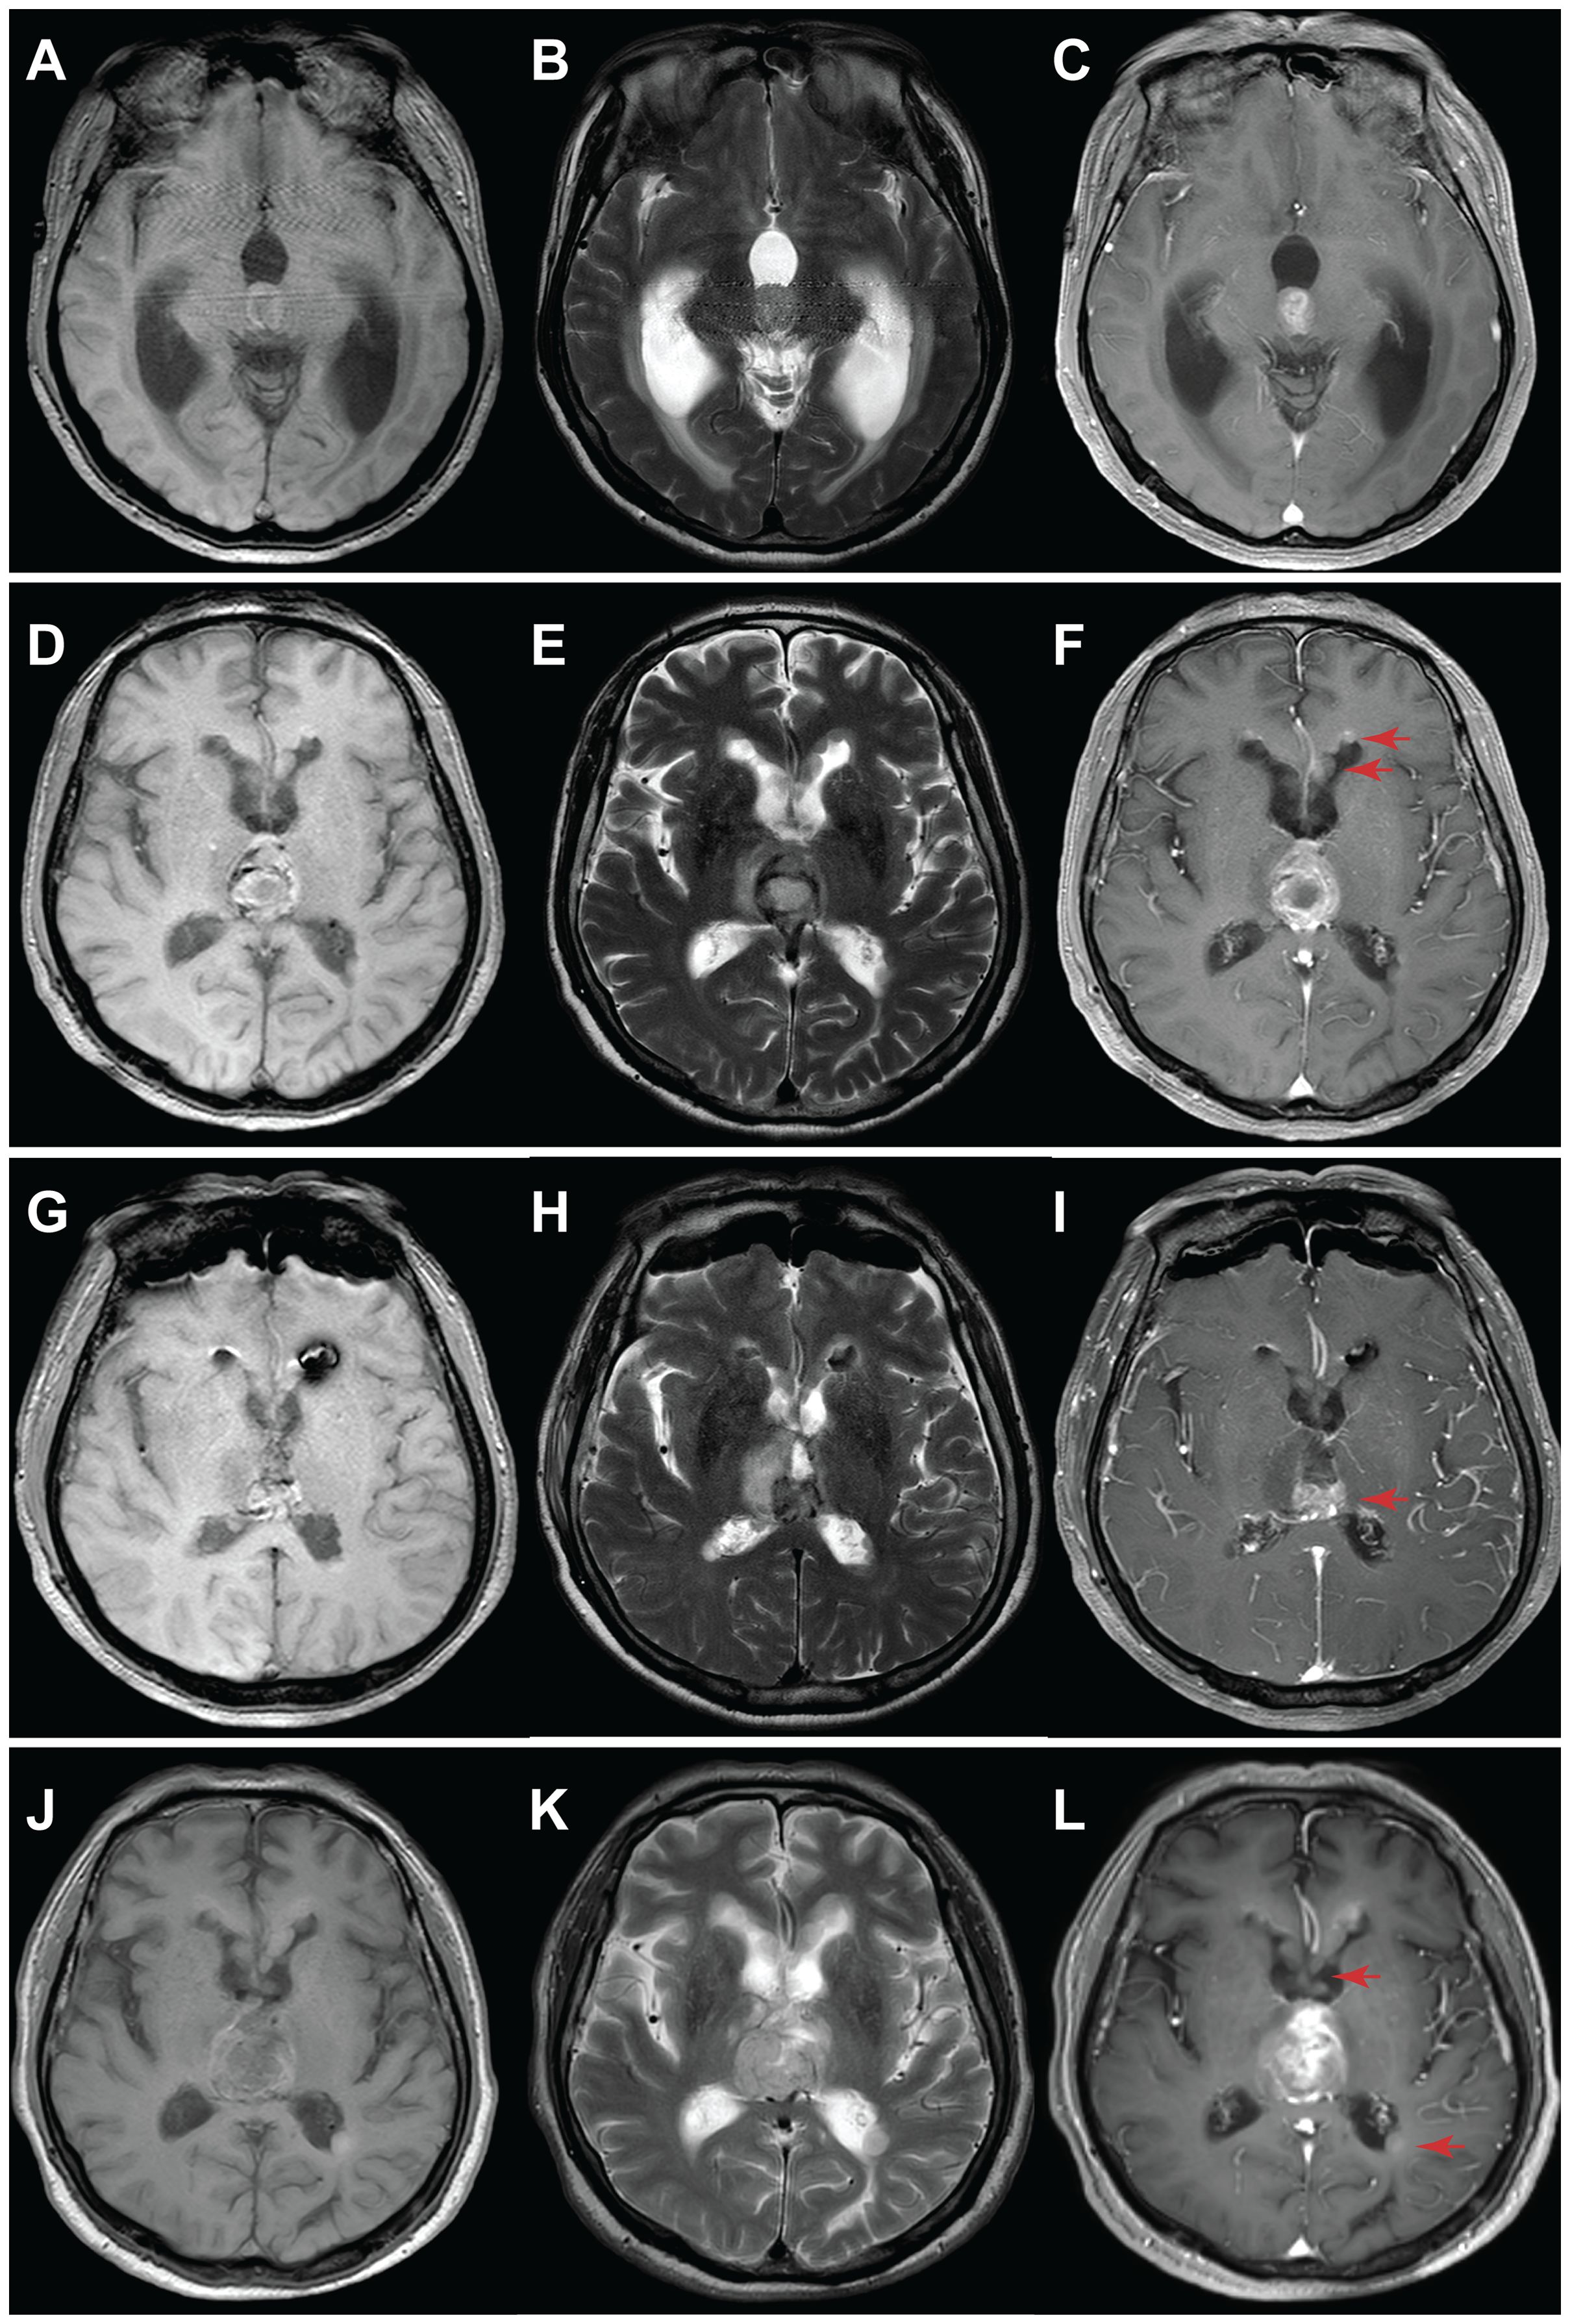

The mitogen-activated protein kinase (MAPK) signaling pathway plays roles in cell proliferation, differentiation, and apoptosis, all crucial for cellular transformation. It's no surprise that MAPK alterations are prevalent in numerous tumors. Several critical genes in the MAPK signaling pathway, including BRAF, FGFR, and NF1, are mutated in brain tumors. For example, FGFR1 mutation or rearrangement has been described in pilocytic astrocytoma, diffuse astrocytoma, and dysembryoplastic neuroepithelial tumor (DNT). These MAPK-activated brain tumors are benign and seldom progress to malignancies, with the mechanisms driving this rare transformation not yet fully understood. In this study, we present two cases of high-grade glioma characterized by a single activating mutation of FGFR1 and massive chromosome loss (near-haploid genome). Similar haploidy is found in 3 additional high-grade astrocytoma by literature review, all harbor a single gene mutation in the MAPK pathway. We propose that the massive chromosome loss might serve as a significant mechanism contributing to the unusual malignant transformation of benign brain tumors activated by the MAPK pathway.